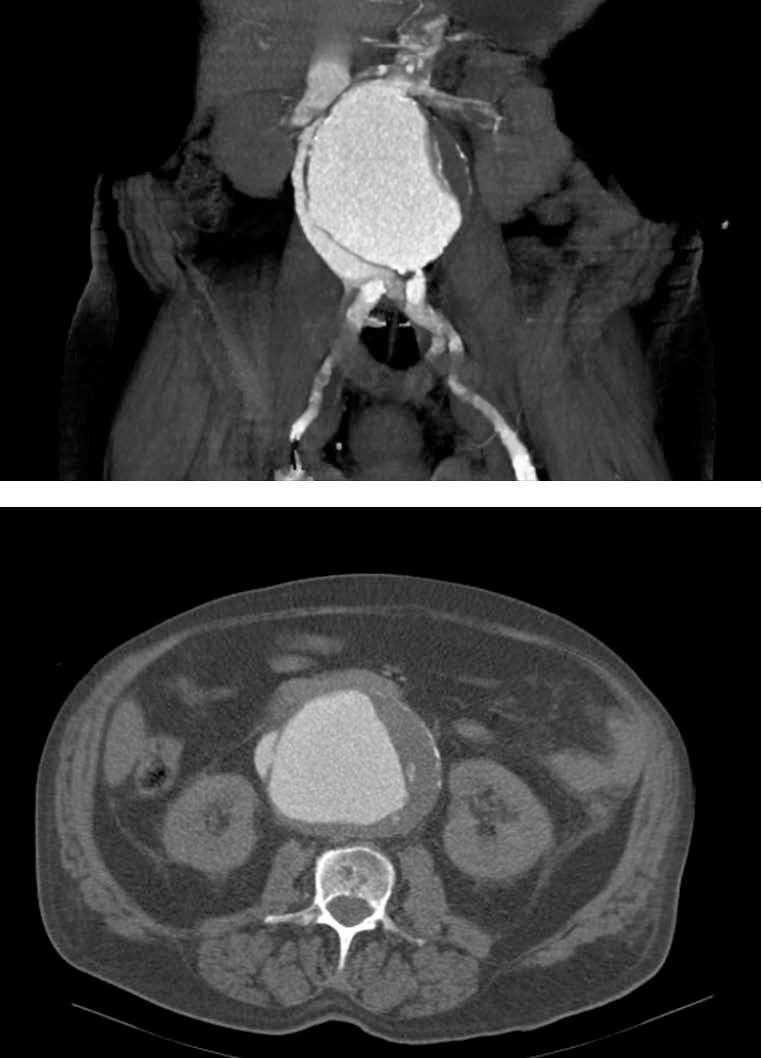

The chest x-ray showed a vascular redistribution pattern with small bilateral pleural effusion. A renal Doppler ultrasound showed normal-sized kidneys without signs of obstruction, a dilated right renal vein, and a large AAA. The CT scan with contrast showed an infrarenal, 10cm AAA with atherosclerosis and thrombosis, without retroperitoneal haematoma, as well as the flow of contrast to the vena cava and right renal vein during the arterial phase and the ACF (Figure 1).

The diagnostic method of choice for ACF is CT, which shows early enhancement of the vena cava, isodense with the aneurysm and even the arteriovenous communication. Other findings include the inferior vena cava dilated or compressed by the aneurysm, retrograde opacification of the renal veins during the arterial phase, poor renal enhancement or an increase in size, and pelvic and retroperitoneal congestion.13,14

Figure 1. CT scan with contrast. Abdominal aorta aneurism and aortocaval fistula